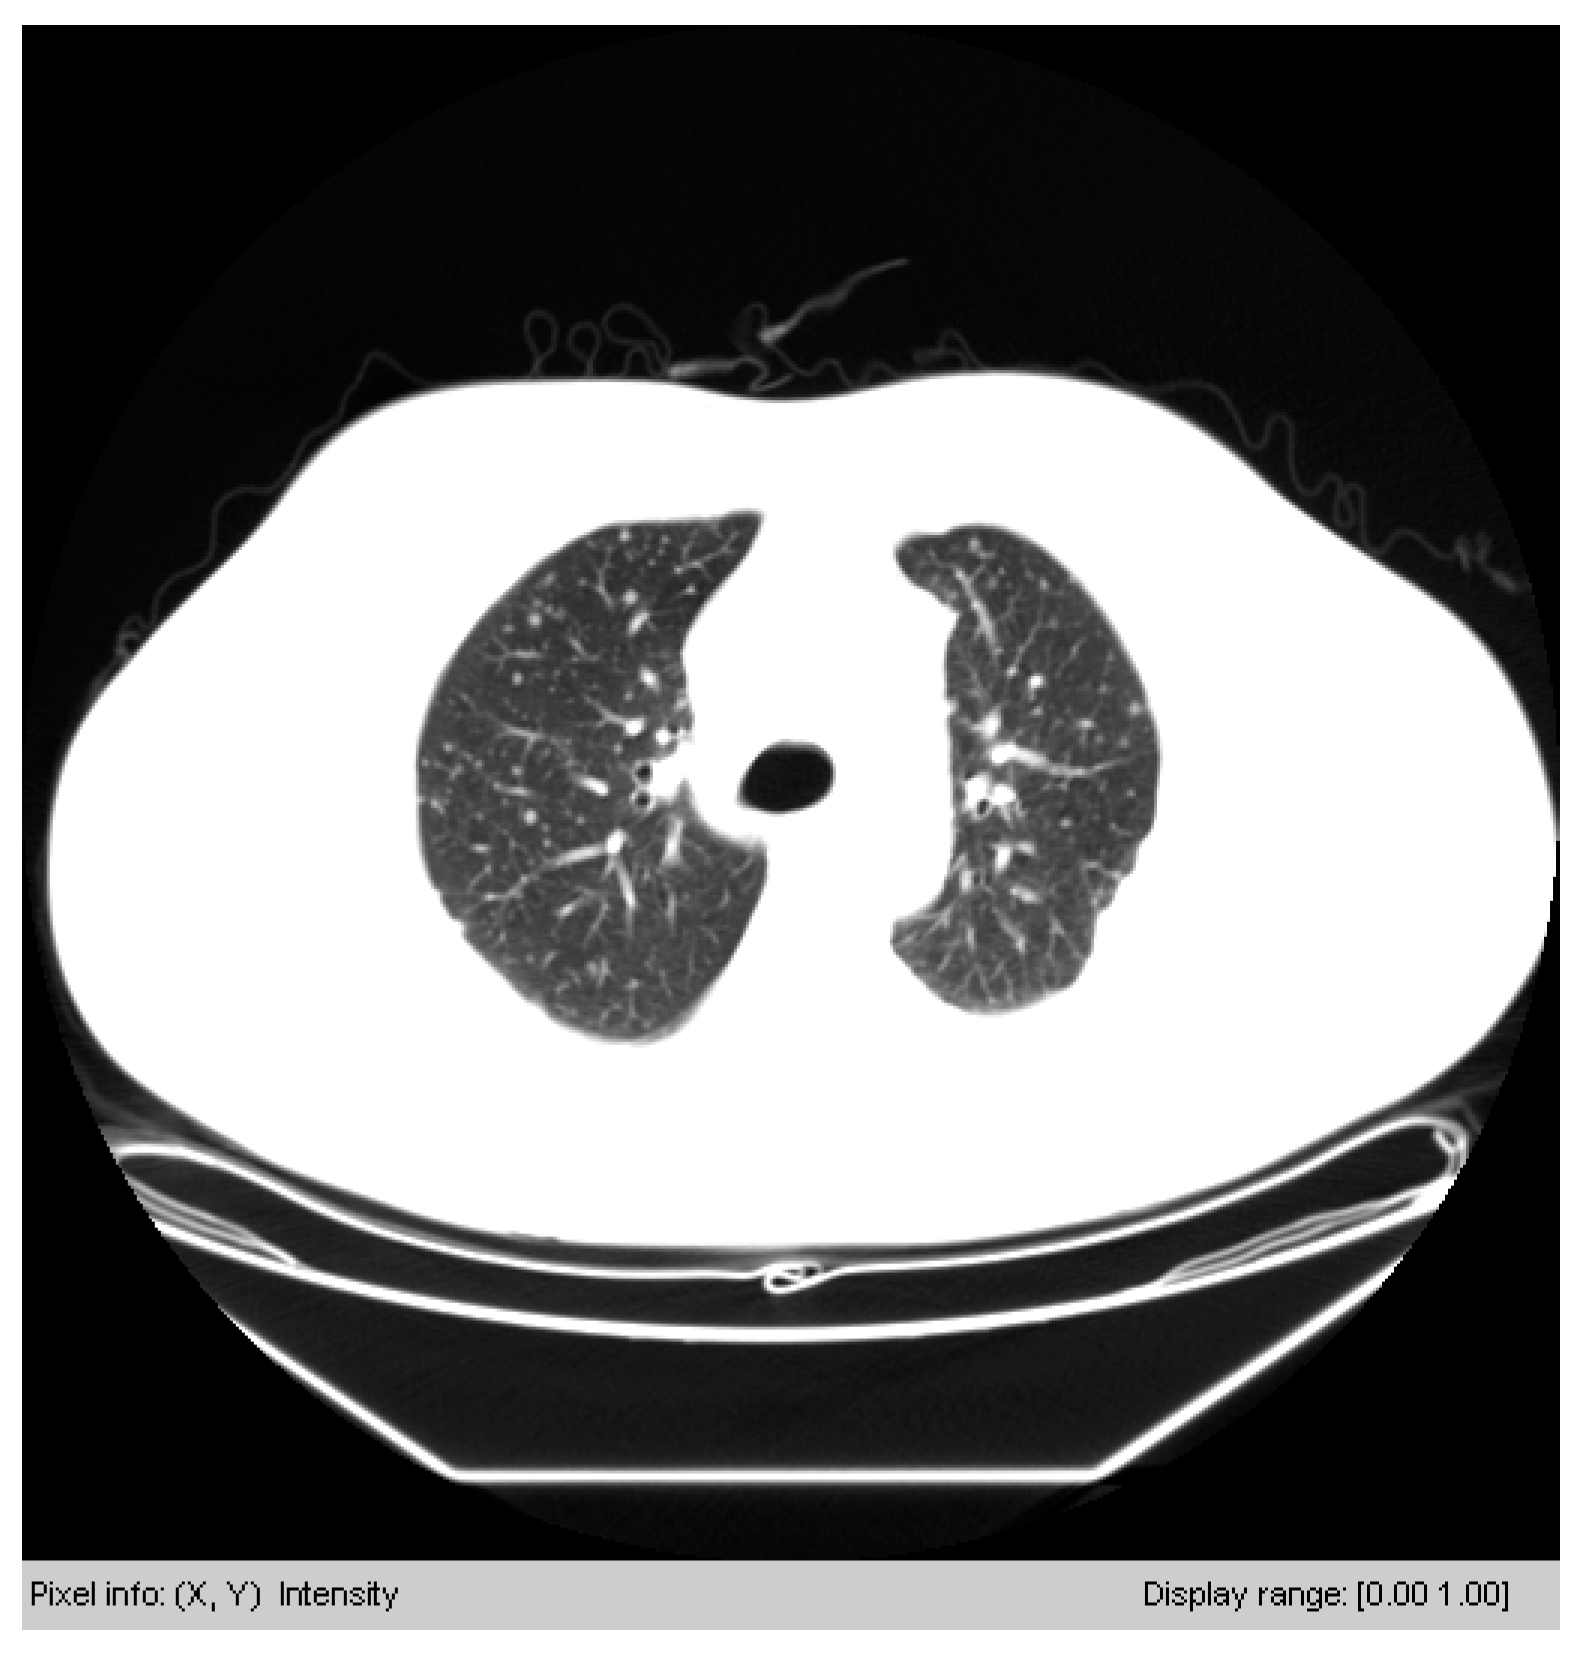

3.3.1. Segmenting the Chest CT Image

3.3.2. Removing Irrelevant Background Areas

3.3.3. Outlining the Lung Areas with a Box Field